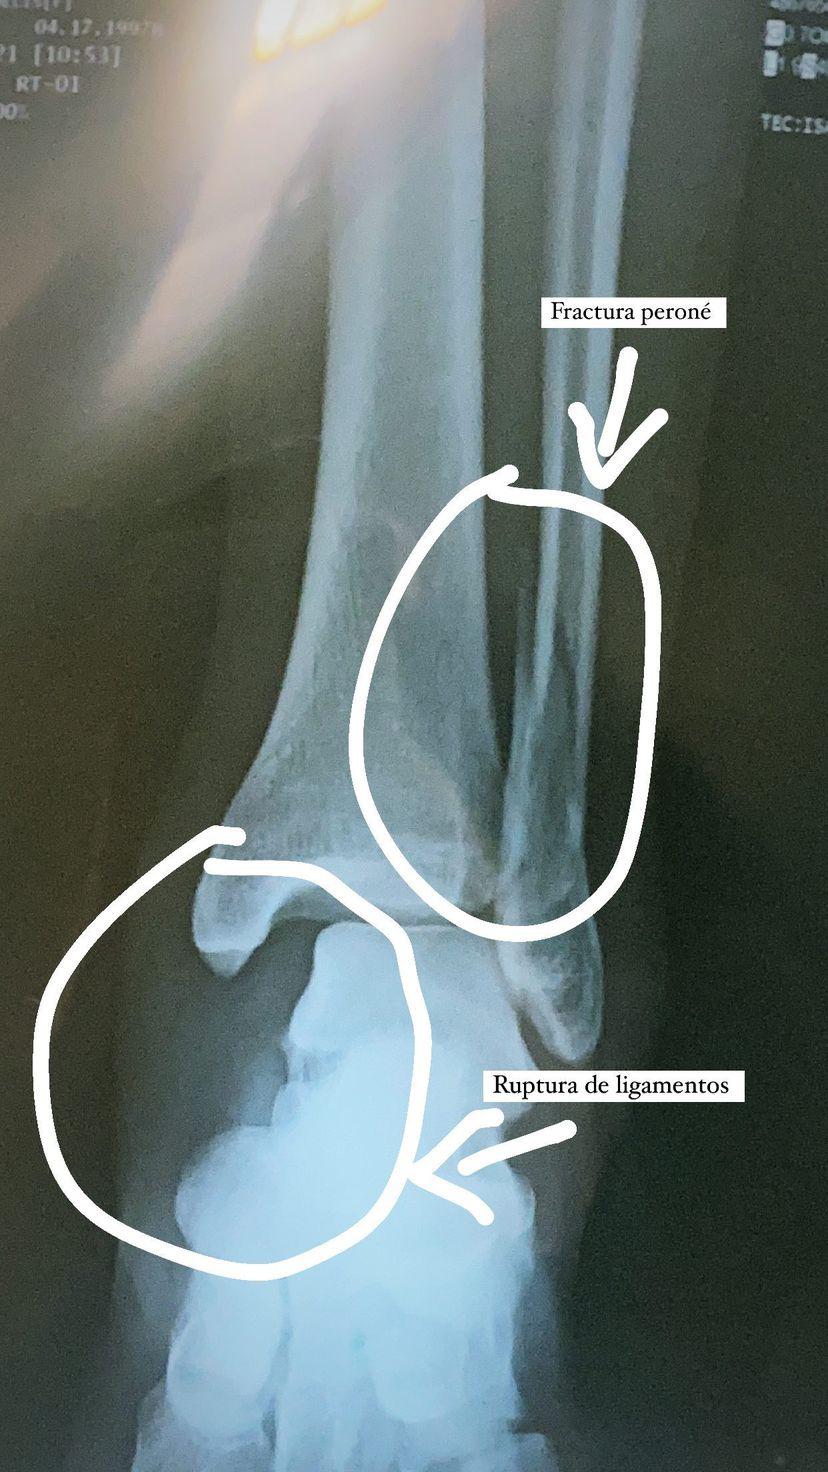

La jugadora sufrió una fractura en el peroné en el arranque de pretemporada de las Cañoneras

MAZATLÁN._ De manera exitosa fue el reporte que resultó sobre la operación a la cual fue sometida la futbolista del Mazatlán FC Femenil, Melisa Ramos, quien sufrió una fractura en el peroné el pasado lunes.

Fue durante el primer día de pretemporada del Mazatlán FC Femenil cuando Ramos se accidentó, donde tras sufrir un percance al resbalar, terminó por fracturarse el peroné y un ligamento.